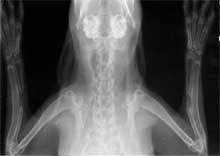

(3)术后分别于2、4、8周行X线、组织病理学检查。采用光镜、组化染色、图象分析等方法检测骨缺损修复的程度。

3. X线、组织病理切片表明BMP+MSC 组术后2周有明显的骨痂生成,术后4-8周连续性骨痂桥接骨缺损,与单纯注射骨髓组有显著性差异。

髓腔形成                              X线4周(BM vs MSC)